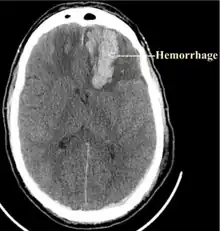

Powassan virus infection is rarely diagnosed as a cause of encephalitis; however, when it is, Powassan encephalitis is severe, and neurologic sequelae are common.[5] Powassan encephalitis has symptoms compatible with acute disseminated encephalomyelitis, oftentimes making it difficult to diagnose.[5] Powassan virus encephalitis is a challenge to diagnose because there are only a few laboratories that offer testing, the most effective being serologic testing.[21]

There are currently no medications or approved vaccines to treat or prevent the POWV. People affected by Powassan virus generally first show symptoms 1 to 3 weeks after infection.[6] The initial symptoms include fever, headache, nausea, occasional confusion, and weakness.[11] With severe Powassan illnesses the victims should be hospitalized, because the symptoms do worsen. If not treated, symptoms could extend to meningoencephalitis, which may include: seizures, aphasia, cranial nerve palsies, paresis and altered mental status.[6][11] Currently, the best ways to treat POWV illnesses include medications to reduce brain swelling, respiratory support and intravenous fluids.[11] About 10% of POWV encephalitis cases are fatal and half the survivors have permanent symptoms that affect their brain.[19] There were 33 confirmed cases of Powassan virus infection in the U.S. between 2001 and 2010.[6]

A rare case of a five-month-old Connecticut infant boy contracting Powassan virus infection was published in 2017. He survived with normal motor and verbal development on follow-up at the age of 10 months, but a head MRI showed severely abnormal brain conditions, including scarring (gliosis) and softening (encephalomalacia) in the thalamus and basal ganglia on both sides, and volume loss and early mineralization in the left basal ganglia.[22]